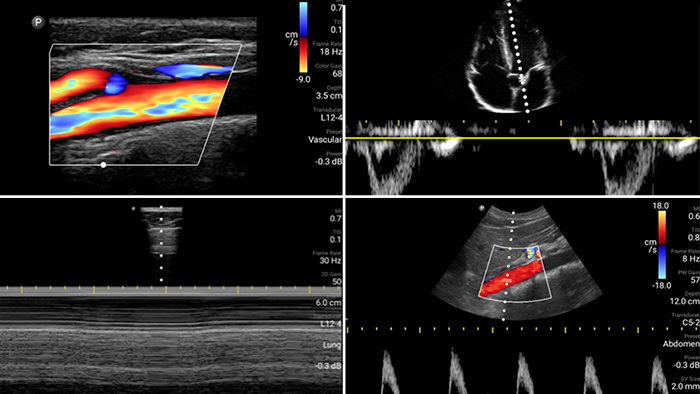

First case image

Lumify is with you

every step of the way

Evaluate, diagnose and treat your patients in

minutes with a multi-point POCUS exam.

Second case image